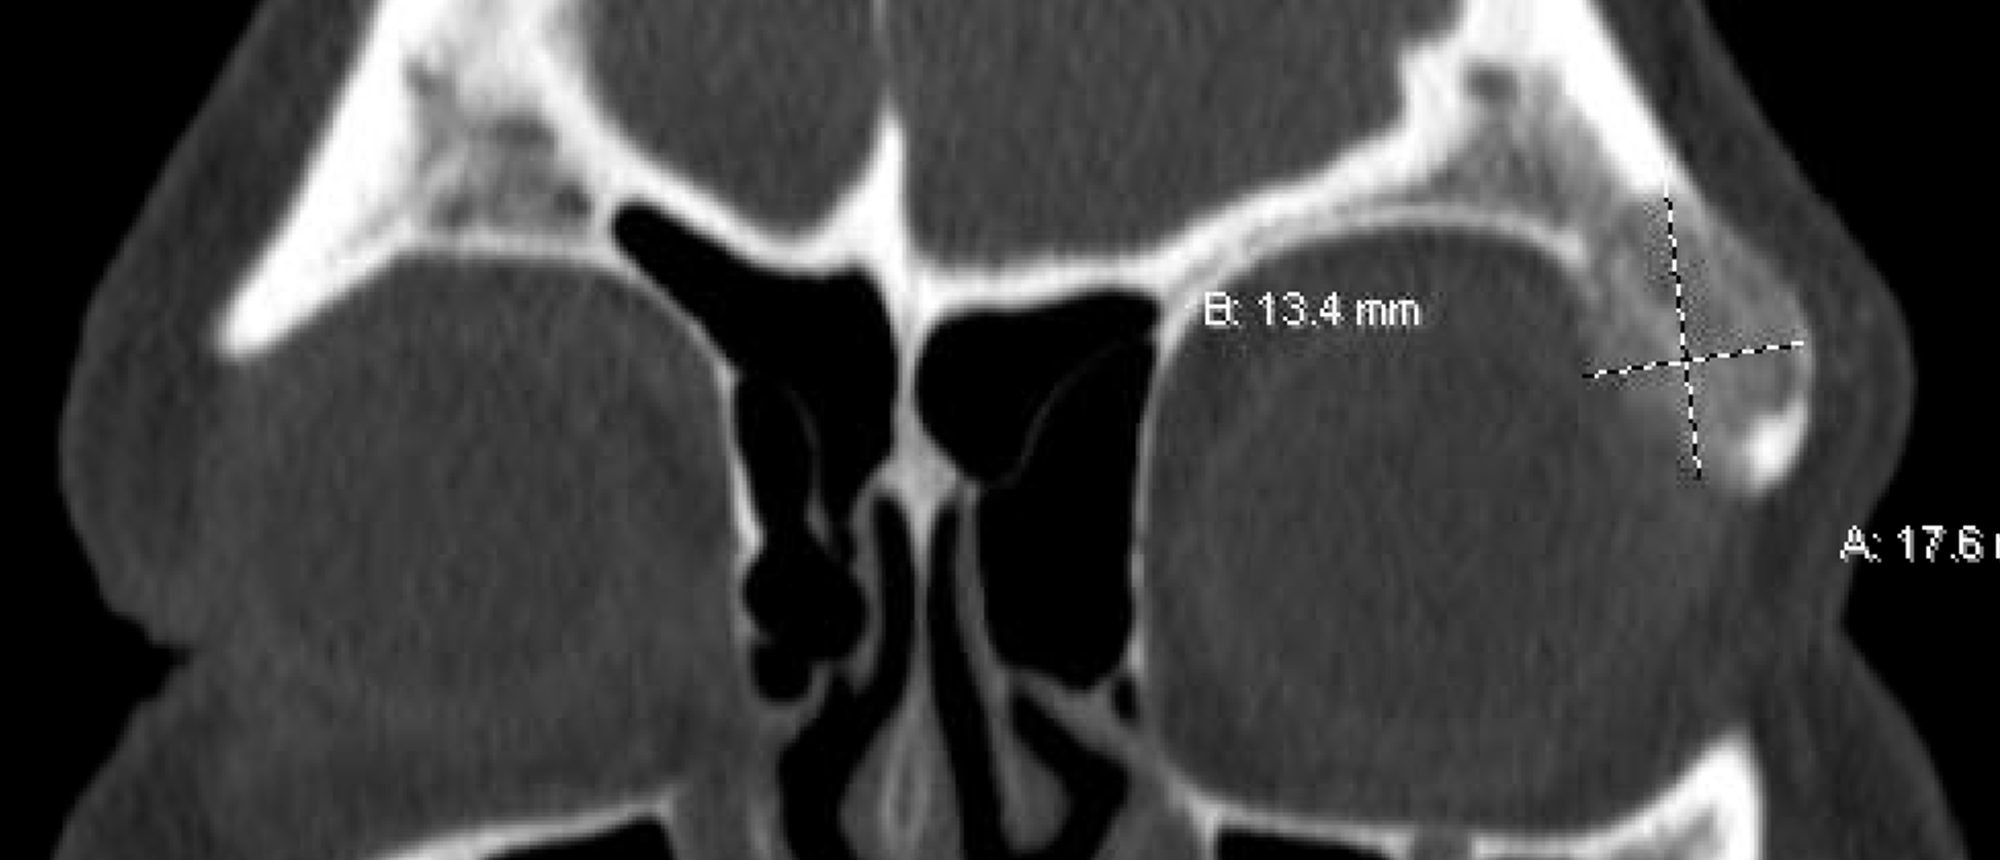

Abstract A patient presented with several weeks of right eye proptosis. On initial examination, his visual acuity in the right eye was 20/400, and a relative afferent pupillary defect was noted. He had 4 mm relative proptosis on the right and restricted motility in all gaze directions. CT orbits re…

NUT Carcinoma A patient presented with several weeks of right eye proptosis. On initial examination, his visual acuity in the right eye was 20/400, and a relative afferent pupillary defect was noted. He had 4 mm relative proptosis on the right and restricted motility in all gaze directions. CT orbi…